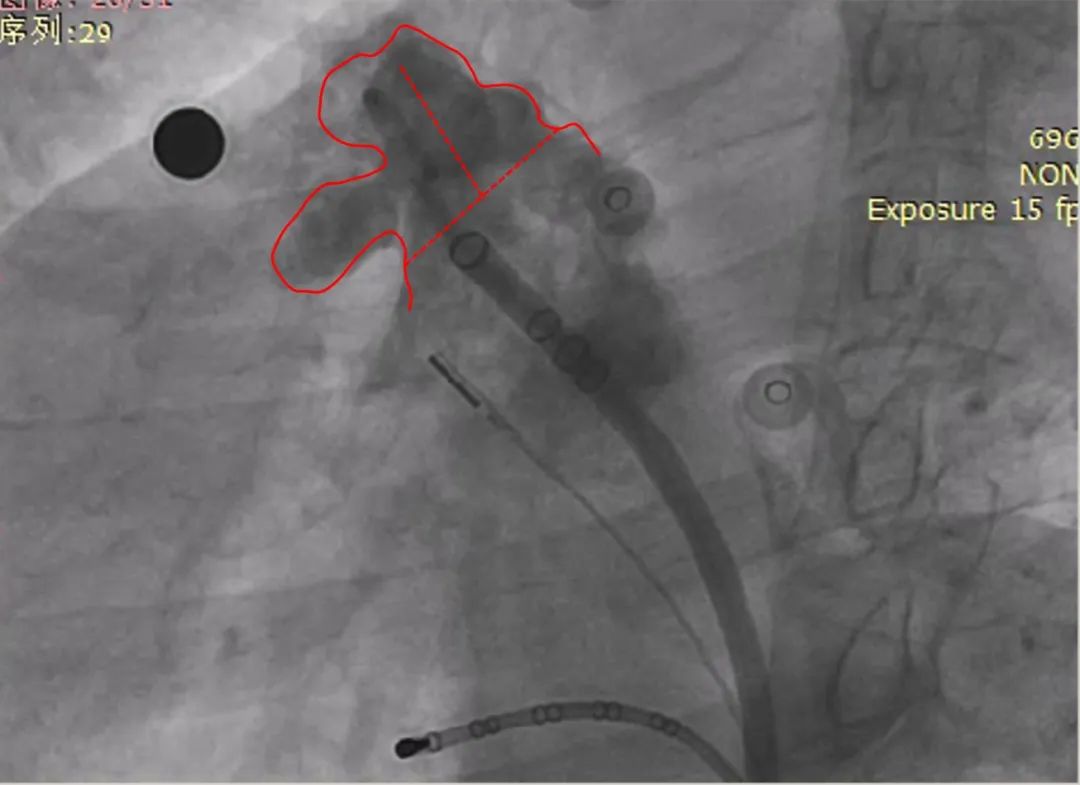

展开后造影

封堵器呈热狗型,下缘轻微露肩

牵拉后再造影

肝位及纯足位下缘轻微露肩(少于封堵器尺寸1/3),肩位下无明显露肩,评估符合PASS原则

LAO 30° CAU 20°

LAO 30° CRA 20°

释放后再造影

释放钢缆后造影,封堵器位置稳定,释放后形态良好